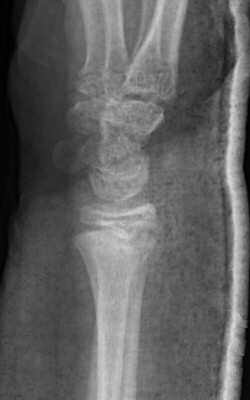

Dorsalbockad distal radiusfyseolys Salter-Harris typ 2 före och efter reposition

Dorsalbockad distal radius- och/eller ulnafyseolys (SH2)

Behandla icke-kirurgiskt om: [1]

- < 10 år för flickor, < 12 år för pojkar:

- ≤ 30° vinkelfelställning jämfört med anatomiskt läge

och

- ≤ 1/2 benbredds ad latus

- ≥ 10 år för flickor, ≥ 12 år för pojkar:

- ≤ 20° vinkelfelställning jämfört med anatomiskt läge

- ≤ 1/4 benbredds ad latus dorsalt

Icke-kirurgisk behandling:

- Semicirkulärt gips på underarmen (hög gipsskena hos små barn, det ramlar annars av), alltså bredare gips som ger trepunktstöd. Dorsalt vid dorsalbockning, volart med handleden dorsalextenderad vid volarbockning.

- Återbesök med röntgenkontroll efter 5-7 dagar [1], förutom vid odislocerad fraktur, då behövs inget återbesök.

- Vid försämrat läge men inom gränsvärde vid återbesöket: ny röntgenundersökning efter ytterligare 5 dagar. [1]

- Avgipsning i hemmet 3-4 veckor efter skadan. [1]

- Undvik risker 2 veckor efter avgipsning. [1]